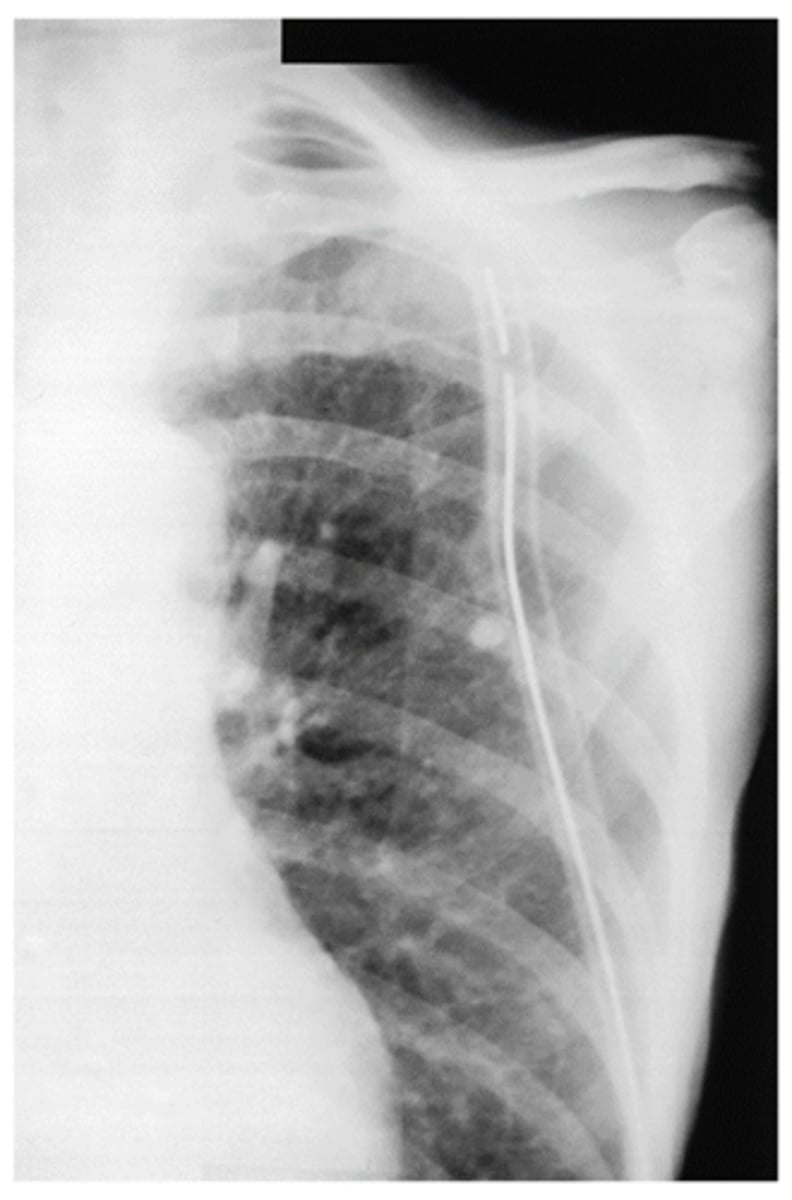

Chest tube (tip of tube should be posterior and near apex of lung for drainage)

What is goin going on in this CXR?